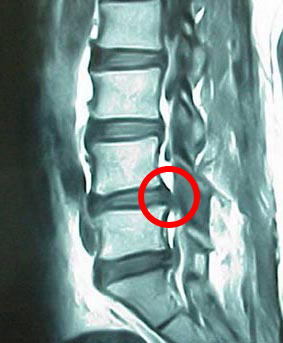

椎間板ヘルニア

脊柱管狭窄症

坐骨神経痛

このような病名をつけられて

このような病名をネットや本やテレビで調べていますよね?

私が言いたいことは1つ!!

本当にそれで痛いんですか???

??

どういう事かと言うと、

痛みが出る一日前に検査しても同じ病名つけられていますよ。

もっというと何ヶ月か前でもつけられています。

何を言いたいかというと、画像上の問題(ヘルニアなど)はあくまで結果で

原因ではないです。

痛みがない人でもヘルニアあるんですよ。